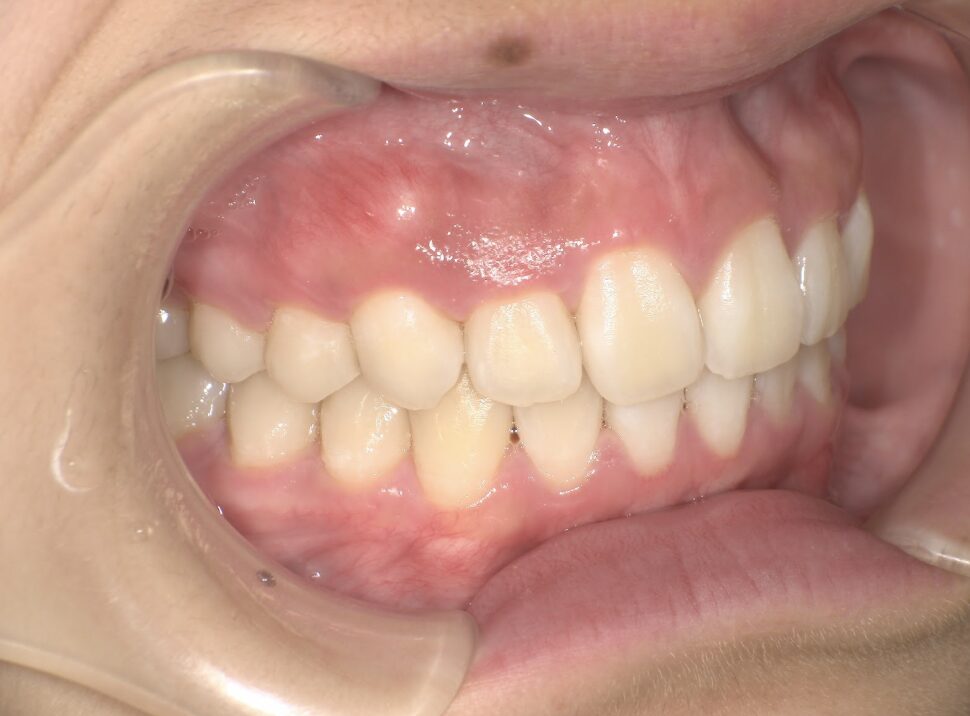

クロスバイト

治療前

ガタガタを主訴に当院を受診され、右上2番にクロスバイトを認めました。IPRを使用してマウスピース型矯正装置(インビザライン)を使用し改善を行いました。